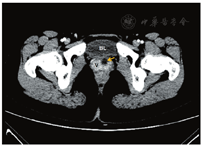

患者女,20岁,因"人工流产术后左下腹痛伴发热2个月余"来我院检查。经阴道超声示:左侧附件区见大小约91 mm×21 mm的无回声包块,其下缘位置较低,达尿道与阴道前壁间隙。初诊超声医生考虑左侧输卵管积脓可能。妇科以"盆腔炎性疾病后遗症:左侧输卵管积脓?"收治入院,完善相关检查后手术。手术前复查超声发现:左肾内可见两组肾窦高回声,上下分布、不相连,其中上组集合系统分离,前后径约41 mm;左侧自上位肾盂发出的输尿管全程扩张,内径约20 mm,下段可见隔膜,隔膜后变细异位开口似与阴道相连(图1)。超声提示:①左侧重复肾,上位肾盂、输尿管积水;②左侧输尿管所见声像,考虑左侧输尿管异位开口于阴道。盆腔磁共振成像(magnetic resonance imaging,MRI)提示:左侧输尿管积水,其末端开口于阴道左前壁,盆腔少量积液。计算机断层扫描尿路造影(computed tomography urography,CTU)提示:左侧重复肾,上位肾盂、肾盏及其连接输尿管明显积水扩张,其末端开口于阴道前壁处,上组集合系统及其连接输尿管未见造影剂填充(图2)。

追问病史,患者口述自幼至今仅在剧烈运动出现阴道漏尿症状,每次数滴。遂诊断为"左侧重复肾,左上输尿管扩张并异位开口于阴道",转诊至泌尿外科,行达芬奇机器人辅助下腹腔镜"左侧重复肾输尿管切除术+左侧肾周粘连松解术+盆腔粘连松解术"。手术结果:左侧完全性重复肾,左侧上位扩张的输尿管末端附着于阴道左前壁处。病理结果:左肾节段性发育不良;左输尿管慢性炎症,部分呈囊性扩张。

最终诊断:左侧完全性重复肾,左侧上位肾盂积水;左侧上位输尿管扩张、末端异位开口于阴道;泌尿系统感染。